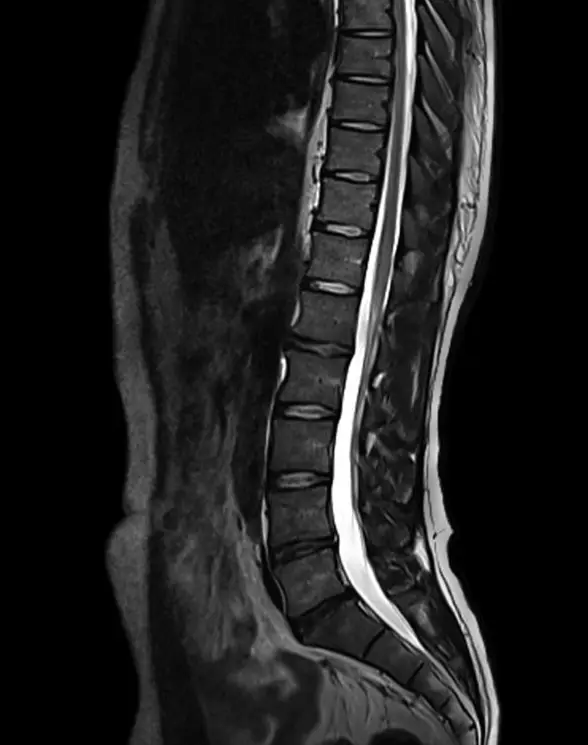

МРТ крестцово-подвздошного сочленения

Визуализация остей подвздошных костей и позвонков крестца.